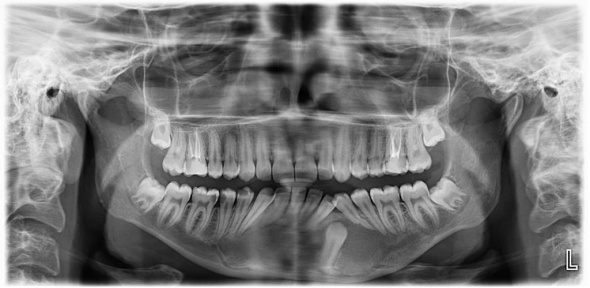

Gömülü bir dişle birlikte 7,5 santimetrelik kistin çene bölgesindeki sinirleri ve kemik yapısını etkilediğini belirten ESOGÜ Ağız, Diş ve Çene Cerrahisi Anabilim Dalı Öğretim Üyesi Doç. Dr. Nesrin Saruhan, hazırlıksız yapılacak ameliyatın büyük risk taşıdığını belirtti. Sinirlerde uyuşukluk ve çene kemiğinde kırık oluşmasını engellemek için kist küçültme ameliyatı yaptıklarını belirten Doç. Dr. Nesrin Saruhan, “Tuğçe bize geldiğinde 15 yaşındaydı. Alt çenesinde sağdan sola uzanan 7,5 santimetrelik oldukça büyük bir kisti vardı. Bununla ilgili birkaç merkeze gitmiş ama Eskişehir’de bu tedavinin yapılamayacağı bilgisi verilmiş. Kendisi kliniğimize geldiğinde önce radyolojik muayenelerimizi yaptık. Oldukça büyük bir kist vardı. Hem sinirle ilişkiliydi hem de alt çene kemiğini zayıflatmıştı. Bir de gömülü dişi vardı. İlk etapta parça alıp biyopsisini yaptık. Kist tanısını koyduktan sonra iki aşamalı tedavi planladık.